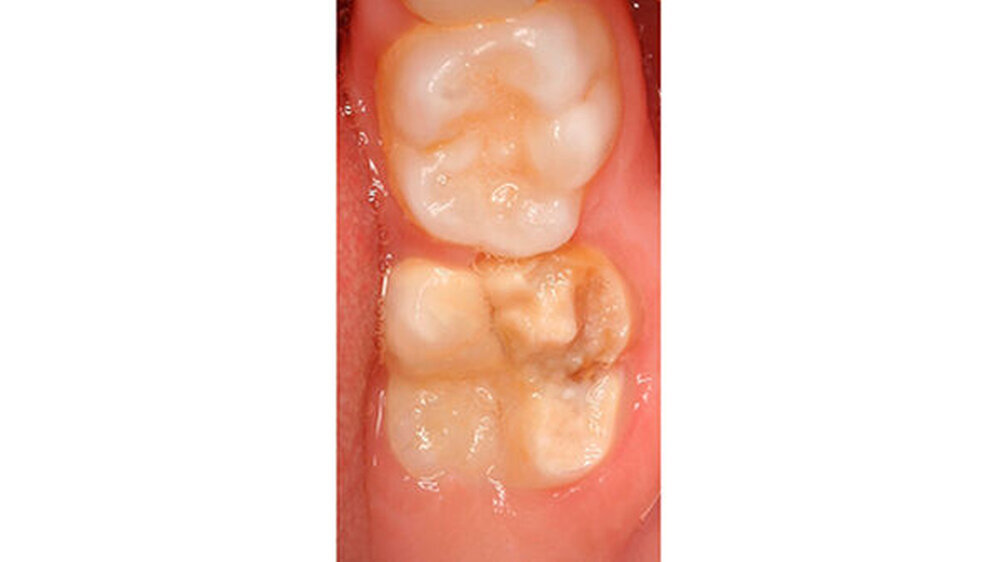

Mit dem Durchbruch der ersten bleibenden Molaren treten dann bisher unbekannte Beschwerden auf wie zum Beispiel eine übermäßig ausgeprägte Kälte-/Wärmeempfindlichkeit. Für manche Kinder wird dadurch nicht nur die Mundhygiene sondern auch die Nahrungsaufnahme erschwert. Zusätzlich bricht oft schon in der Durchbruchs-Phase der Schmelz ein (Abbildung 1), was die Überempfindlichkeit in teils akute Zahnschmerzen übergehen lässt.

Das klinische Bild der MIH reicht von einem bis zu vier betroffenen Molaren, nur selten sind alle Zähne in ähnlicher Ausprägung geschädigt [Weerheijm et al., 2001]. Die bleibenden Frontzähne können ebenfalls betroffen sein, diese weisen allerdings in der Regel keinen Schmelzeinbruch auf und sind selten bis gar nicht überempfindlich [Weerheijm et al., 2001] (Abbildung 2).